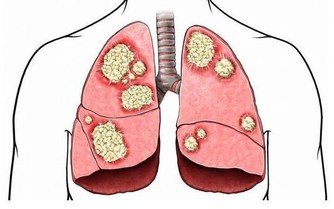

這些都是濕氣重的症狀,濕氣是人類健康的主要威脅。它雖然不是病,但是又比病更威脅。

濕氣重,我們治療的方法都是以清熱祛濕為主。平時多吃健脾利胃的食物,如薏米、冬瓜、苦瓜等。